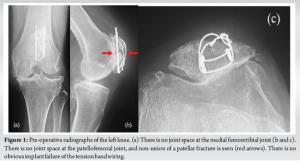

An 85-year-old female visited our hospital complaining of left knee pain. She had undergone ORIF with tension band wiring (TBW) for a left patellar fracture 7 months previously at a different hospital. However, bone union of the patellar fracture had not been achieved and the left knee pain persisted. She had a history of right patellar fracture and fractures of both ankles. Her body mass index was 25.6 kg/m2 (height, 157 cm; weight, 63.0 kg). Because of the left knee pain, she needed support for walking indoors and used a wheelchair outdoors. On physical examination, the range of motion (ROM) of the left knee was 0–120°. The pain was present at the medial joint space and around the patella, where it was particularly severe, with a Numerical Rating Scale (NRS; 0–10) of 8. Both of these areas were tender on palpation. No ligamentous instability was observed. Her Knee Society (KS) knee score was 53, and her KS function score was 40. Bone mineral density of the lumbar spine and proximal femur were 1.305 g/cm² and 0.678 g/cm², respectively. Radiographs of the left knee showed non-union of the patellar fracture, no joint space at the patellofemoral or medial femorotibial joints, and evidence of OA at the level of Kellgren–Lawrence classification stage IV at both of these sites (Fig. 1). Computed tomography (CT) of the left knee also showed non-union at the middle of the patella (Fig. 2). The femorotibial angle was 179°. There was no obvious implant failure of TBW. The diagnosis was severe knee OA with patellar non-union after a previous ORIF. As treatment for the patellar non-union and bone fragility, we initially treated the patient with low-intensity pulsed ultrasound (LIPUS) (Exogen Ultrasound Bone Healing System; Bioventus, Durham, NC) and teriparatide injection (Teribone; Asahi Kasei Pharma, Tokyo, Japan). LIPUS (1.5 MHz) was applied to the affected area for 15 min every day. As there was insufficient improvement in both the subjective symptoms and imaging findings in the left knee after 1 year of treatment, we decided to perform TKA and surgery for non-union of the patella in a one-stage procedure.